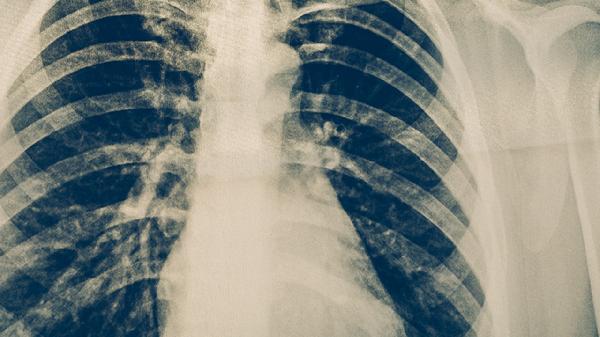

胸部X线检查是肺结核筛查的重要手段,能发现肺部浸润、空洞、纤维化等典型改变。CT检查能更清晰地显示病变细节,对早期病变和肺外结核的诊断价值更高。影像学检查不能单独确诊肺结核,需结合临床表现和其他实验室检查结果。肺结核的影像学表现多样,需与肺炎、肺癌等疾病进行鉴别。